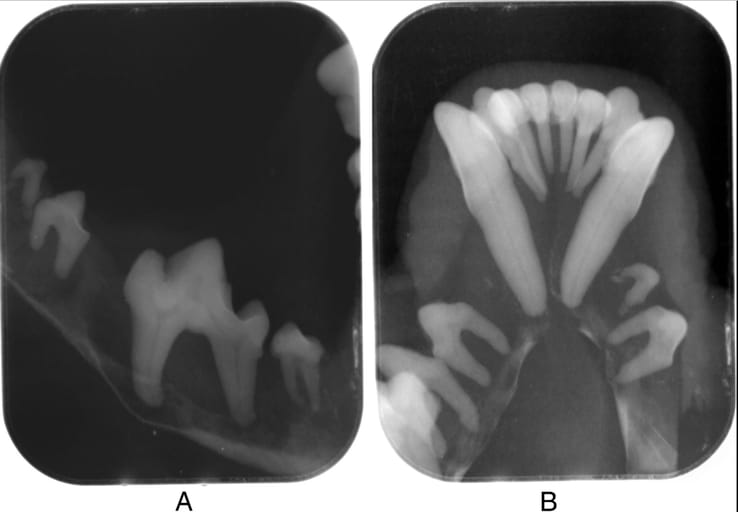

Both dogs exhibited severe oral symptoms, including mobile teeth, halitosis, and mandibular pliability, with radiographs revealing extensive bone resorption in the mandibles and maxillae. Laboratory tests confirmed severe azotemia, hyperphosphatemia, and anemia, consistent with CKD. Despite medical management, both patients deteriorated and were euthanized within two to three months of diagnosis. Histological findings confirmed chronic kidney disease with interstitial fibrosis, glomerular abnormalities, and tubular degeneration.

Case 2. Intraoral radiographs showing severe osteopenia, loss of lamina dura, interradicular and interdental bone, thin mandibular cortex with no uniform density. (A) Lateral left first molar and mandible. (B) Ventrodorsal view of rostral mandible.